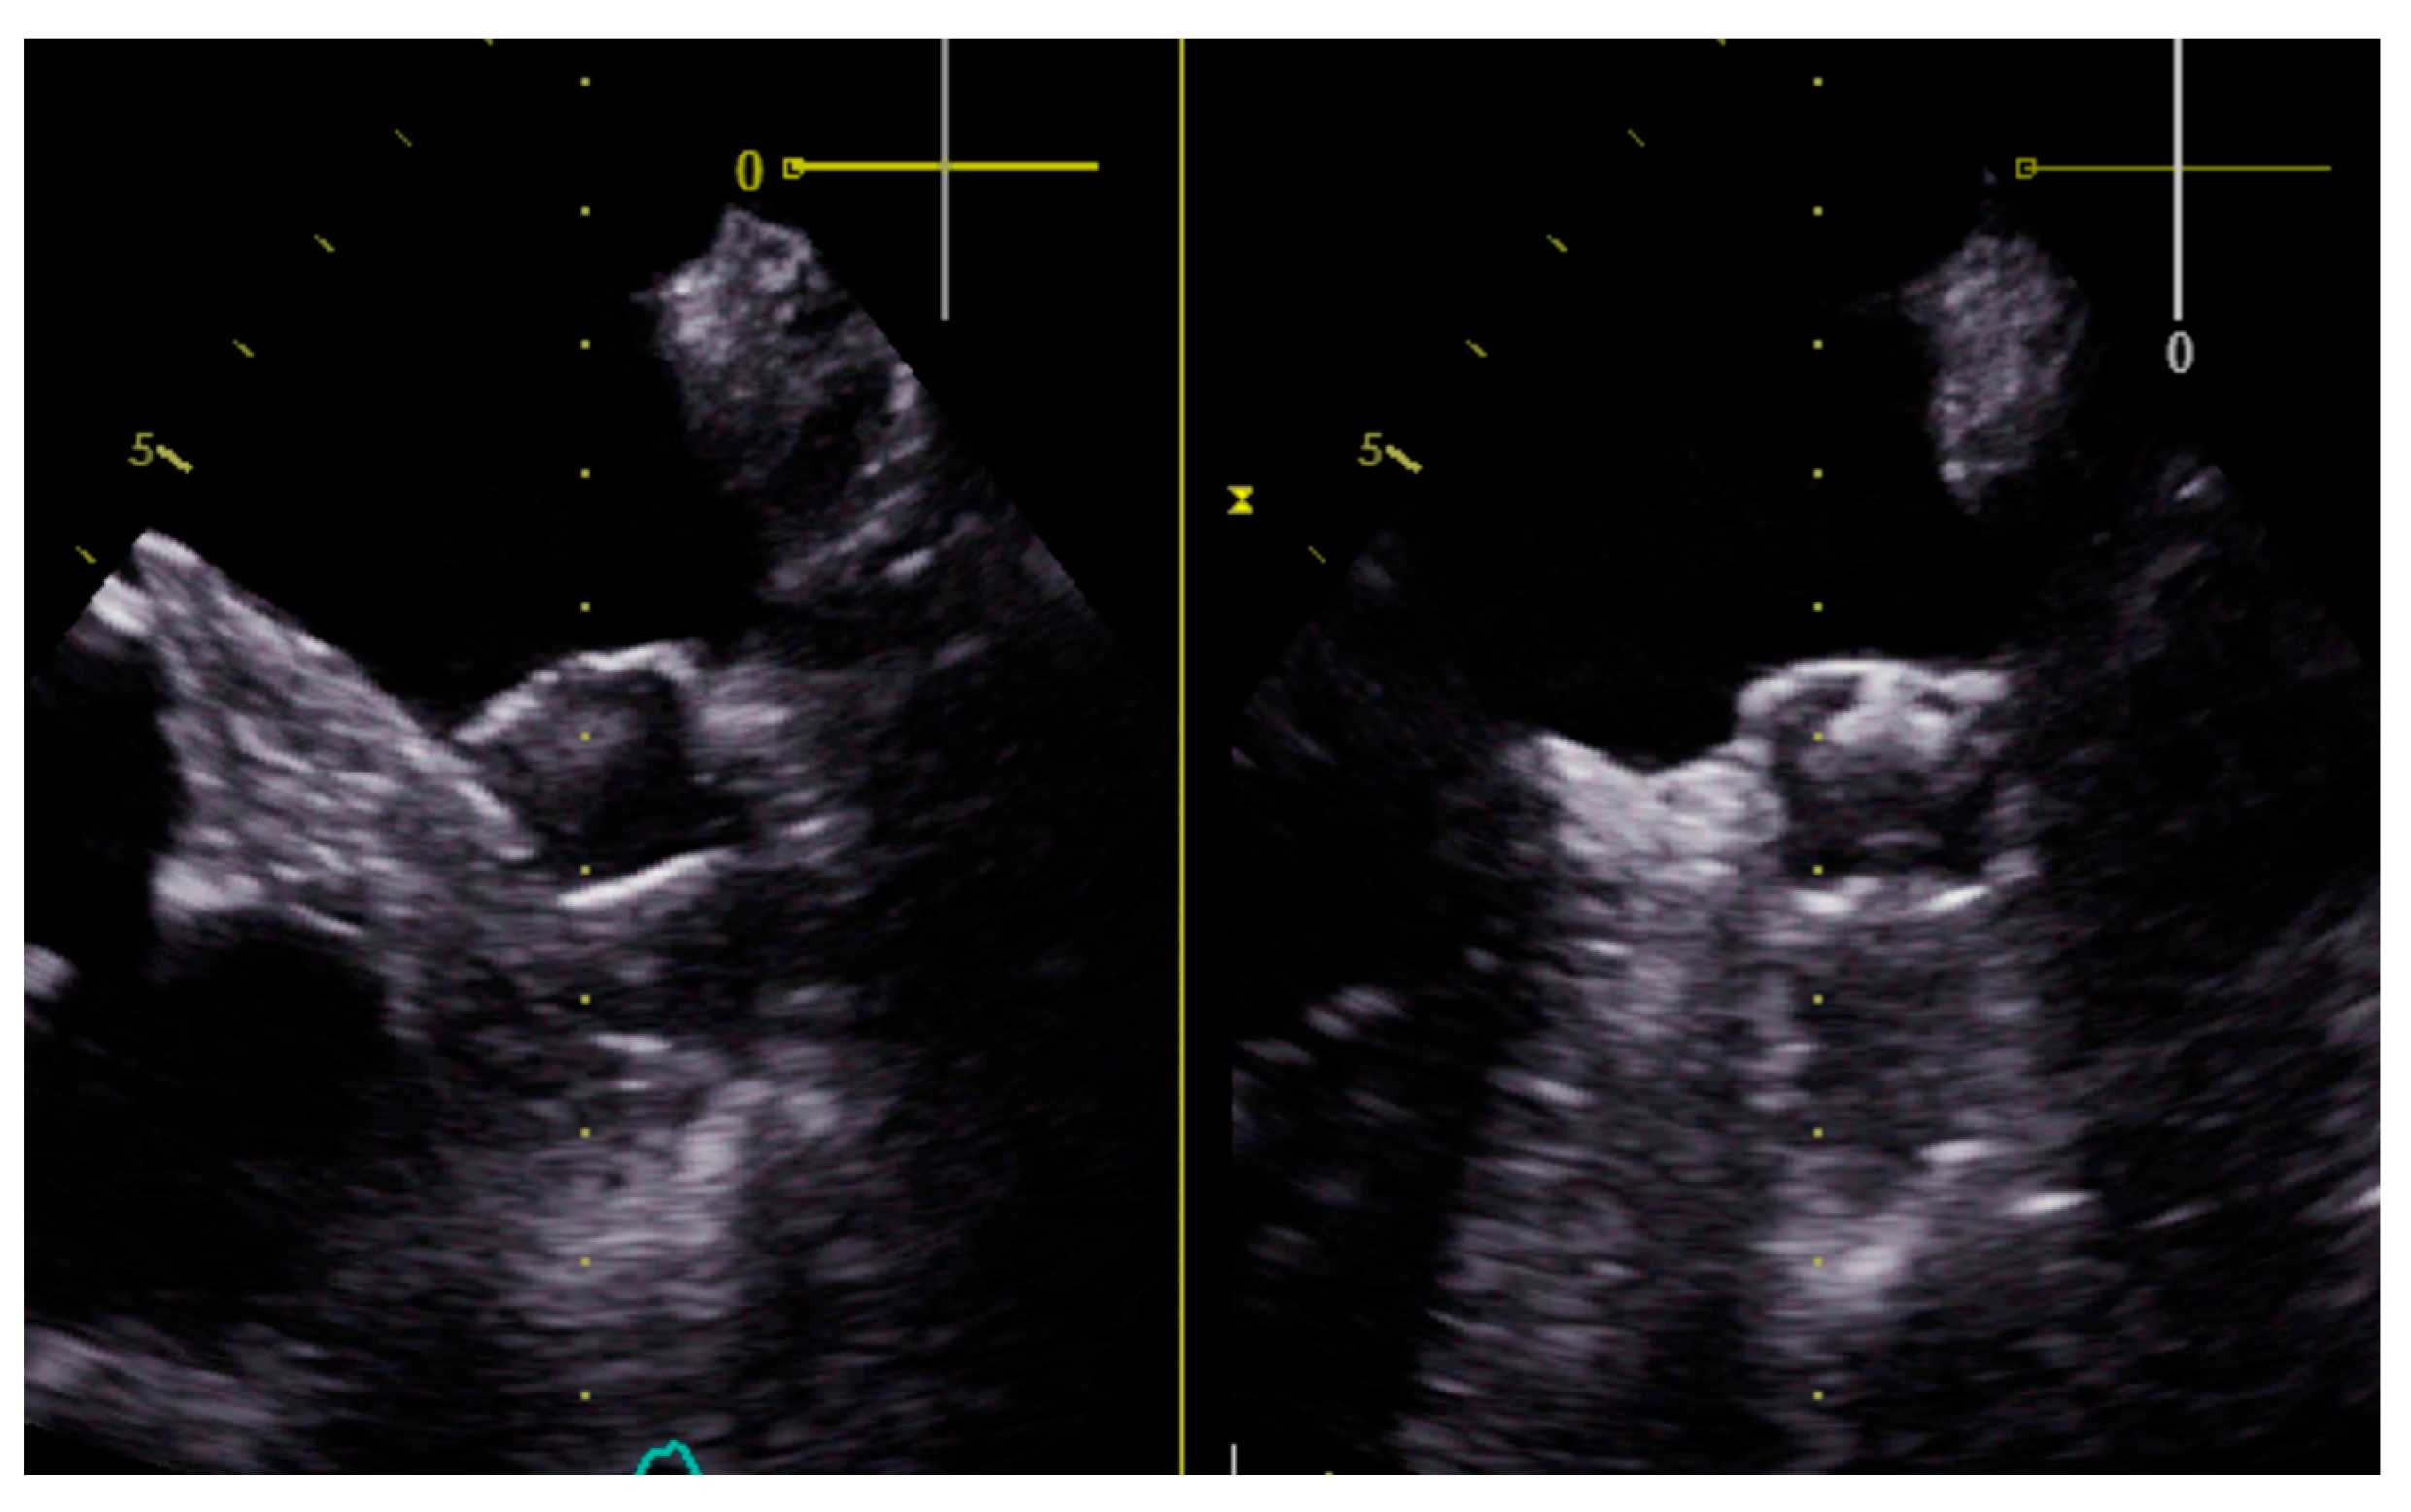

| LAAC device | Watchman FLX 27 mm | Watchman Flx 24 mm | Watchman Flx 24 mm | Watchman Flx 24 mm | Watchman FLX 24 mm | Watchman FLX 24 mm | Watchman FLX 31 mm | Watchman FLX 24 mm |

| Thrombosis or leaks at 3-month control echocardiogram | No | No | No | Yes (leak < 3 mm) | No | No | … | No |